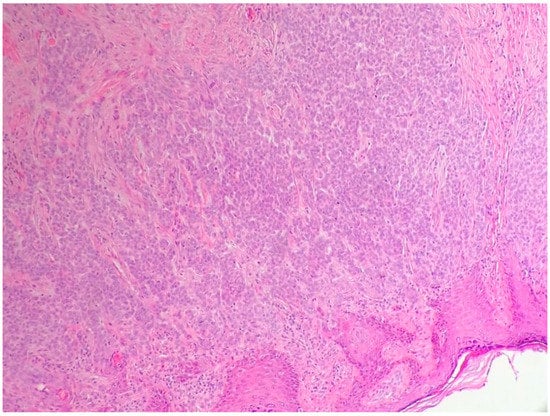

2.2. The Histologic Features of Actinic Keratosis, Bowen’s Disease, and Squamous Cell Carcinoma

2.2.3. Main Histologic Variant and Differential Diagnoses of NMSC with Squamous Differentiation